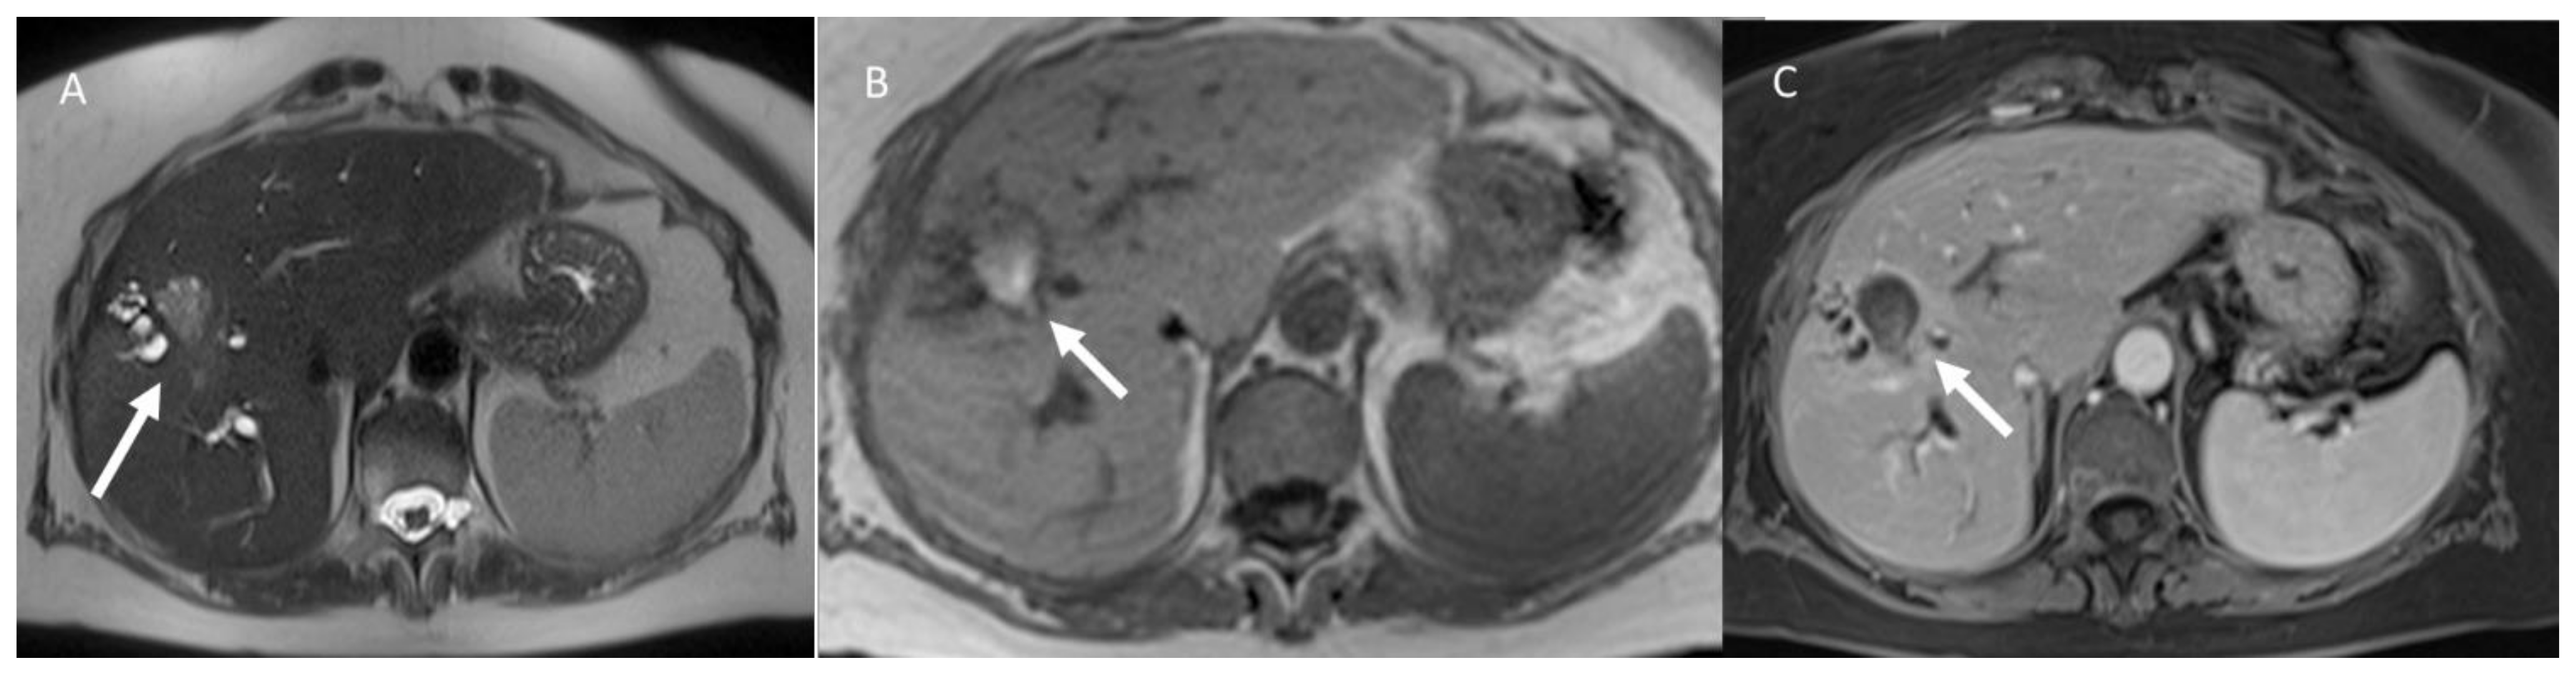

- Granata, V.; Fusco, R.; Catalano, O.; Piccirillo, M.; De Bellis, M.; Izzo, F.; Petrillo, A. Percutaneous Ablation Therapy of Hepatocellular Carcinoma with Irreversible Electroporation: MRI Findings. Am. J. Roentgenol. 2015, 204, 1000–1007. [Google Scholar] [CrossRef] [PubMed]

- Granata, V.; Castelguidone, E.D.L.D.; Fusco, R.; Catalano, O.; Piccirillo, M.; Palaia, R.; Izzo, F.; Gallipoli, A.D.; Petrillo, A. Irreversible electroporation of hepatocellular carcinoma: Preliminary report on the diagnostic accuracy of magnetic resonance, computer tomography, and contrast-enhanced ultrasound in evaluation of the ablated area. Radiol. Med. 2016, 121, 122–131. [Google Scholar] [CrossRef]